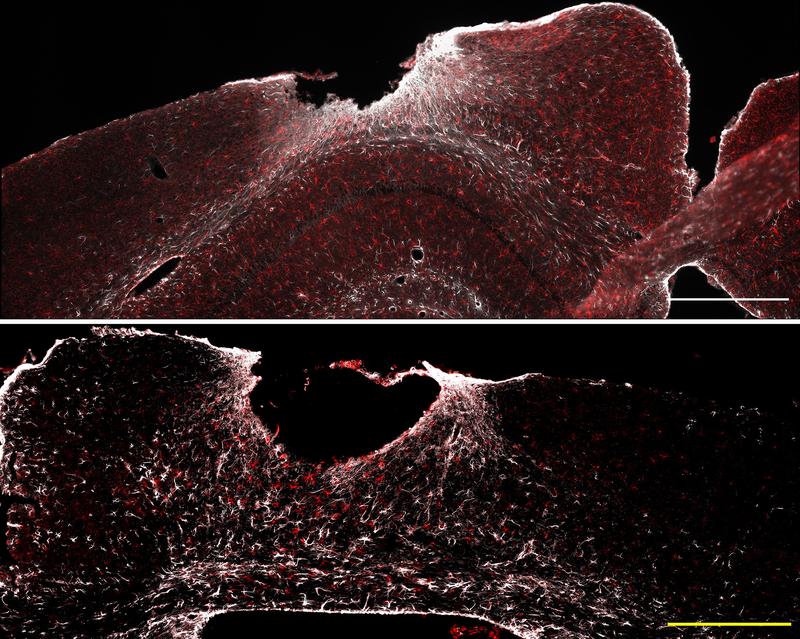

The star-shaped glial cells also play a key role in the wound healing and scar formation process of injured brain tissue. "At the injury/damage site, astrocytes surround the wound core. In this way, they limit further neurodegenerative processes and support healing," explains Professor Leda Dimou. The head of the Department of Molecular and Translational Neurosciences at the Department of Neurology also played a leading role in the study. The researchers found a striking gene expression signature in the immediate vicinity of the insult area indicating a particularly high NF-κB activity in astrocytes. To investigate the influence of NF-κB in more detail, the researchers worked with mouse models. In these, NF-κB was either pre-activated or strongly inhibited in astrocytes. The team wanted to know: Does this modulation improve or worsen healing after traumatic brain injury?

The result was clear: If NF-κB was pre-activated, the immune system reacted more rapidly and stronger to the traumatic injury. This excessive neuroimmune response triggered detrimental inflammatory processes and disrupted both wound healing and scar formation.

"Certain immune cells such as dendritic cells unexpectedly migrated into the wound area. This prevented coordinated scar tissue formation, which ultimately led to neurological deficits," report the study's first authors, Tabea M. Hein and Ester Nespoli. Surprisingly, similar processes occur in the ageing brain. However, when NF-κB was inhibited in astrocytes, single positive effects were observed: Antioxidant defense and mitochondrial function improved, for example. "However, these changes were not sufficient to significantly improve the healing process in general," explain the researchers.

Even though some questions remain unanswered, the results provide important insights for new therapeutic strategies. The role of certain glycoproteins found in bone metabolism is particularly striking. For example, osteopontin (OPN), which is important for tissue formation and wound healing, is insufficiently produced when there is excessive NF-κB activation in the area of injury thus impairing healing. In contrast, more lipocalin-2 protein (LCN2) is produced. This protein can promote harmful neuro-inflammatory processes and can impair the maintenance of the blood-brain barrier. "This could lead to new therapeutic approaches by specifically regulating the levels of these two factors," says Bernd Baumann. The research project was funded as part of two Collaborative Research Centers based at Ulm University, including CRC 1149 "Danger Response, Disturbance Factors and Regenerative Potential after Acute Trauma" and CRC 1506 "Aging at Interfaces".